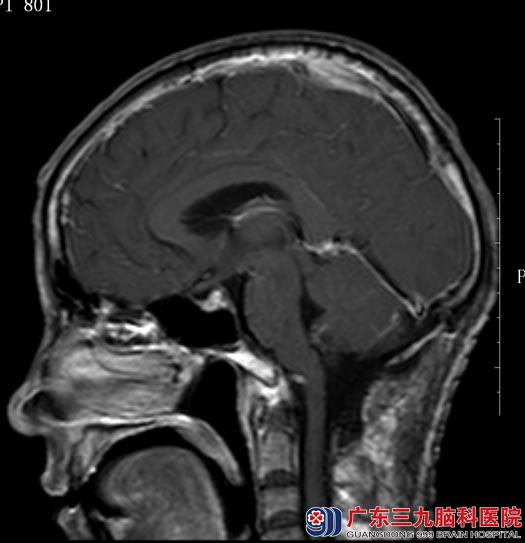

5月11日,鲁明主任主刀行 “右侧小脑半球血管母细胞瘤切除术”。术中见右侧小脑半球局部膨隆,压力较高,先用脑穿针穿刺放出部分淡黄色囊液,脑压下降,再切开脑皮层,显微镜下见红褐色肿物,直径约2cm,周围血管丰富,予电凝烧灼供血动脉,完整切除肿瘤,术中未输血。术后,田师傅的头痛、头晕症状缓解,四肢活动良好,病理结果示“血管母细胞瘤”。

▲▂手术后